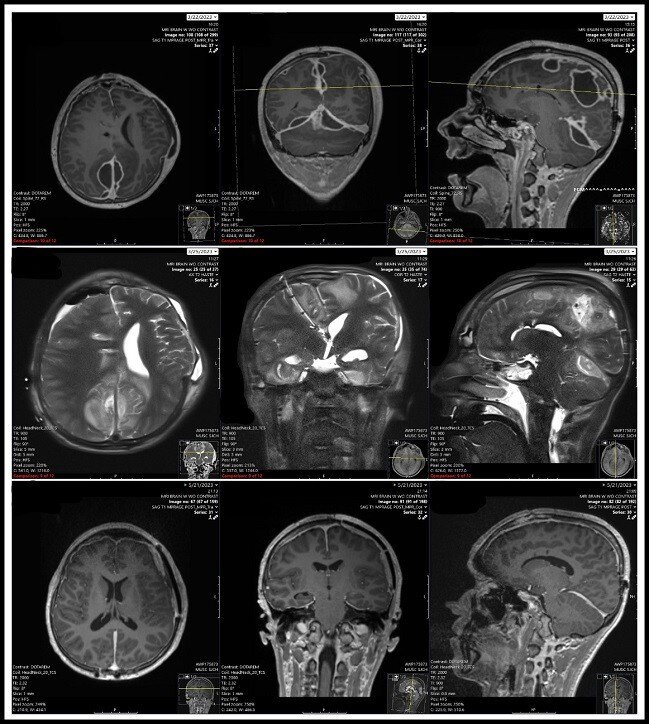

Top row: scan indicates pockets of pus in brain

Middle row: scan shows skull after over 12 surgeries and half of the skull was removed and brain was drained. An induced COMA due to brain pressures that would normally kill a patient.

Bottom row: scan shows complete recover, patient walking around and out of rehab. t.